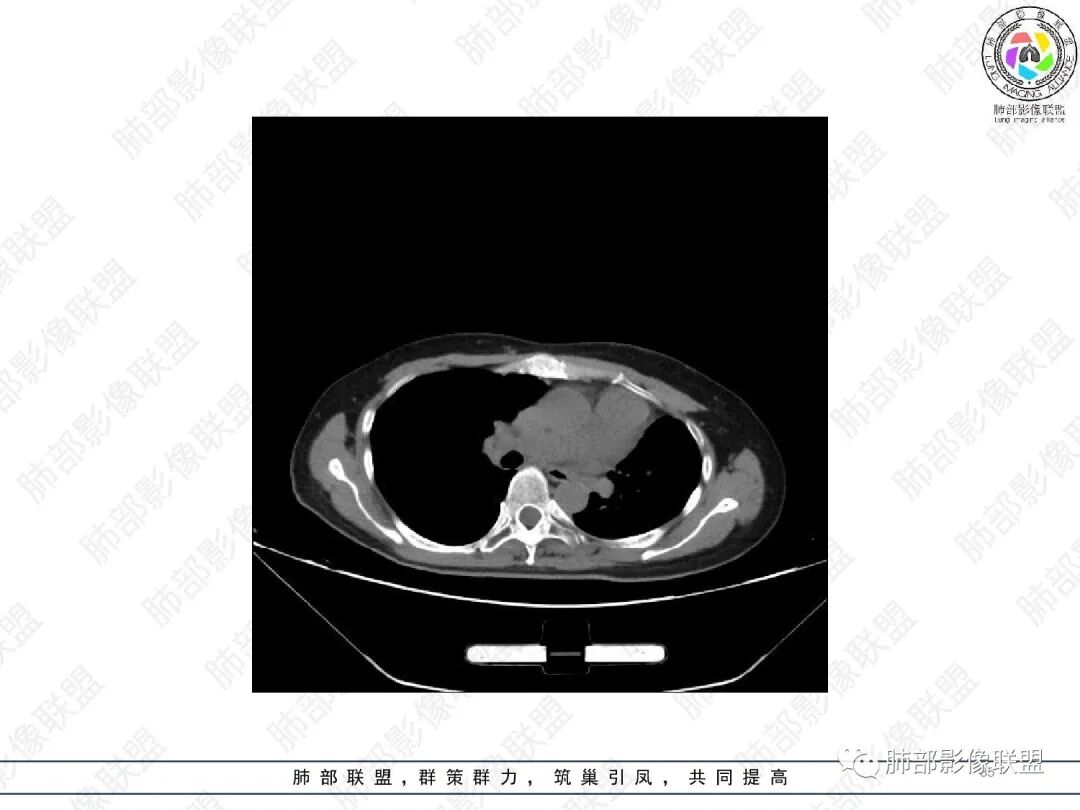

1.中年女性,主因“咳嗽、咳痰半年余”入院,既往史:8年前因左肺病在外院变行左肺叶切除术,诉术后抗结核治疗1年,具体病理等不详。实验室IGE显著增高。

2.胸部CT:右肺上叶及中叶不规则块状影,沿支气管走行方向指套样影,支气阻塞湖嵌塞,腔内可见高密度影。灶周可见磨玻璃,外围见结节影及树芽征。左肺体积缩小,见不规则条索影、胸膜增厚,纵隔牵拉左移。

3.综合分析:结合患者病史及胸部CT主要鉴别ABPA(右肺上叶不规则块影,指套样顺延支气管方向,抗结核治疗1年,肺部病灶仍明显)及继发性肺结核TB(右肺上叶不规则肿块,其可见高密影,边缘模糊,周围卫星灶、树芽征,沿支气管爬行)。